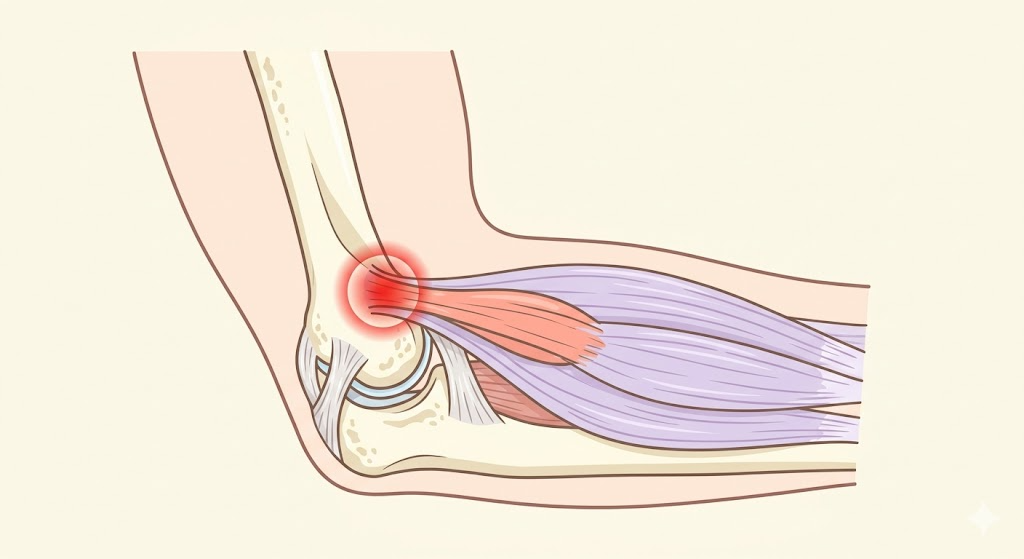

テニス肘の正式名称は「上腕骨外側上顆炎(じょうわんこつがいそくじょうかえん)」といいます。肘の外側にある出っ張り(外側上顆)に付着する腱や筋肉に、繰り返しの負担がかかって炎症が起きる状態です。

痛む場所の特徴

- 肘の外側の骨のすぐ下あたりが痛む

- 痛みは前腕(ひじから手首にかけて)に広がることがある

テニス肘の直接的な原因は、手首を反らす動作(伸筋)の使いすぎです。特に「短橈側手根伸筋(たんとうそくしゅこんしんきん)」という筋肉の付け根に微細な断裂が生じることで痛みが起きます。